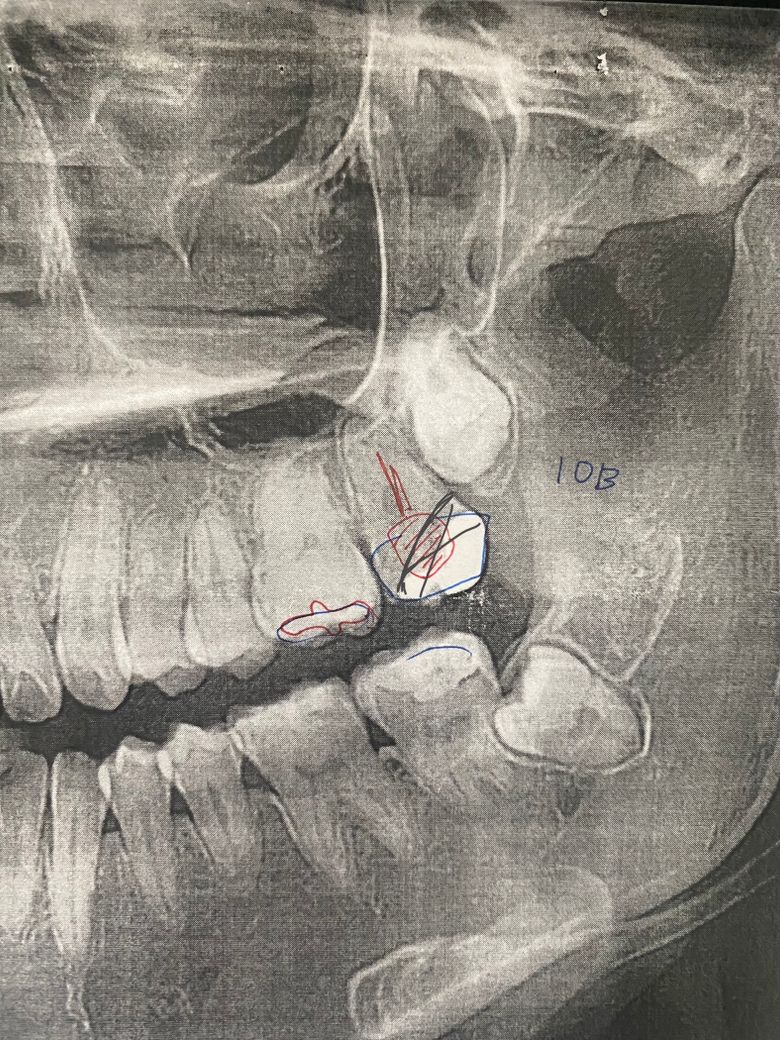

검은색 표시만큼 치아가 삭제 된 것 같습니다.

부분 신경치료 후 검은색깔 재료로

붙여놨구요,

치아 삭제량이 많아 크라운도 못한다고 하시더라구요.

임플란트할 때 뼈가 부족하면 또 비용 추가된다고 하더라구요. 이 사진으로 봤을때 잇몸뼈가 부족한가요?

치아에 염증이 많아 보이진 않아서 뼈이식을 하지 않아도 될것같긴합니다. 하지만 정확한건 CT도 찍어보셔야될것같습니다.

사진상 뼈이식이 필수적으로 보이진 않습니다만 사실엑스레이 사진 하나로 판별하긴 어렵습니다.

치아의 머리 부분에 삭제가 많이 되어 있어도 치아뿌리가 튼튼하게 고정되어 있다면 기둥을 세워서 치아를 사용할 수 있는 경우도 있습니다. 염증이 없는 부위에 치아를 발치할 경우에는 일반적으로 골이식을 하지 않는 경우가 많습니다.

위 사진 보다는 ct가 임플란트 식립을 위해 필요할 것 같습니다. 잇몸뼈가 아주 부족하진 않겠으나 그건 또 수술 하면서 잇몸을 열어보고 상황판단을 해야 할 수도 있습니다.